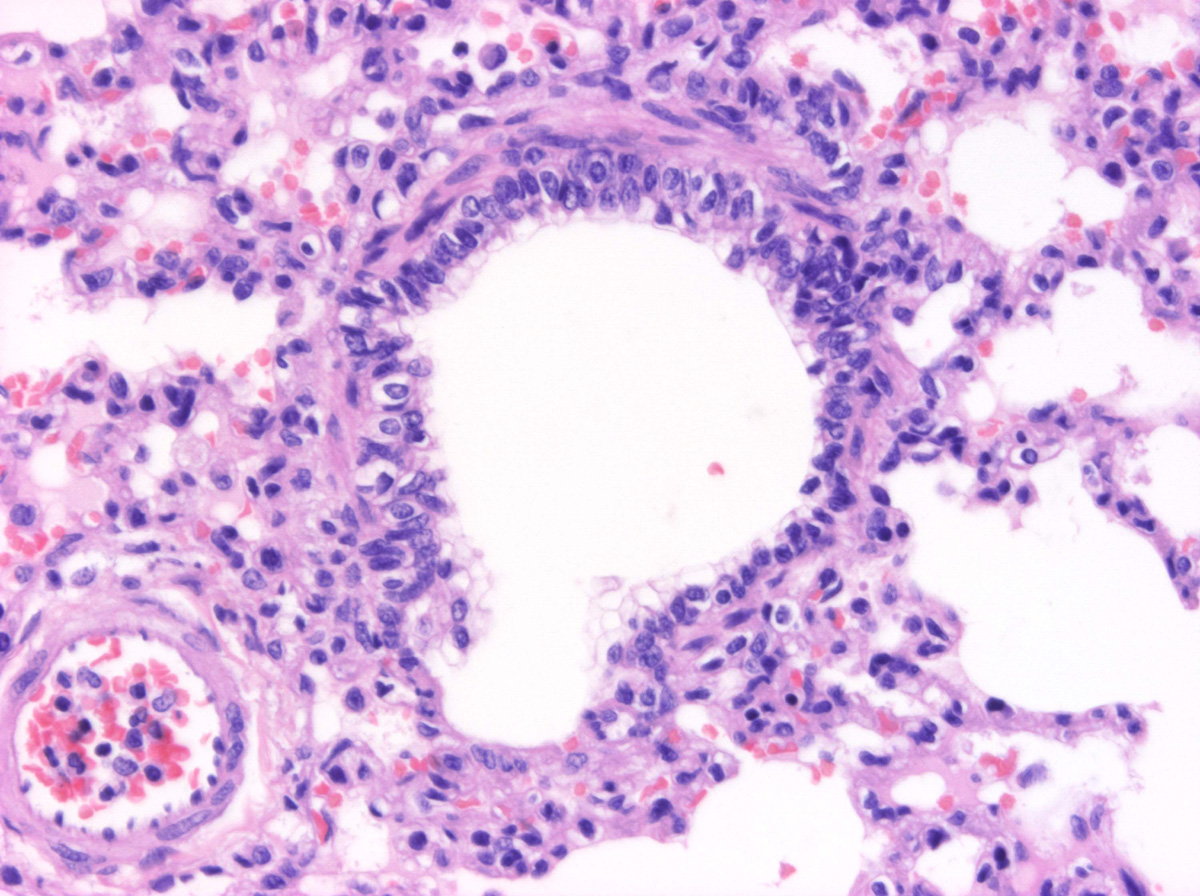

En los bronquiolos, el epitelio respiratorio llega a ser simple, constituido por una única capa de células cilíndricas bajas o cúbicas (en los bronquiolos de menor calibre), ciliadas, células caliciformes y células de Clara. Conforme disminuye la luz, pierden el tejido linfoide, las glándulas y por último el cartílago, quedando reforzados únicamente por tejido muscular liso.